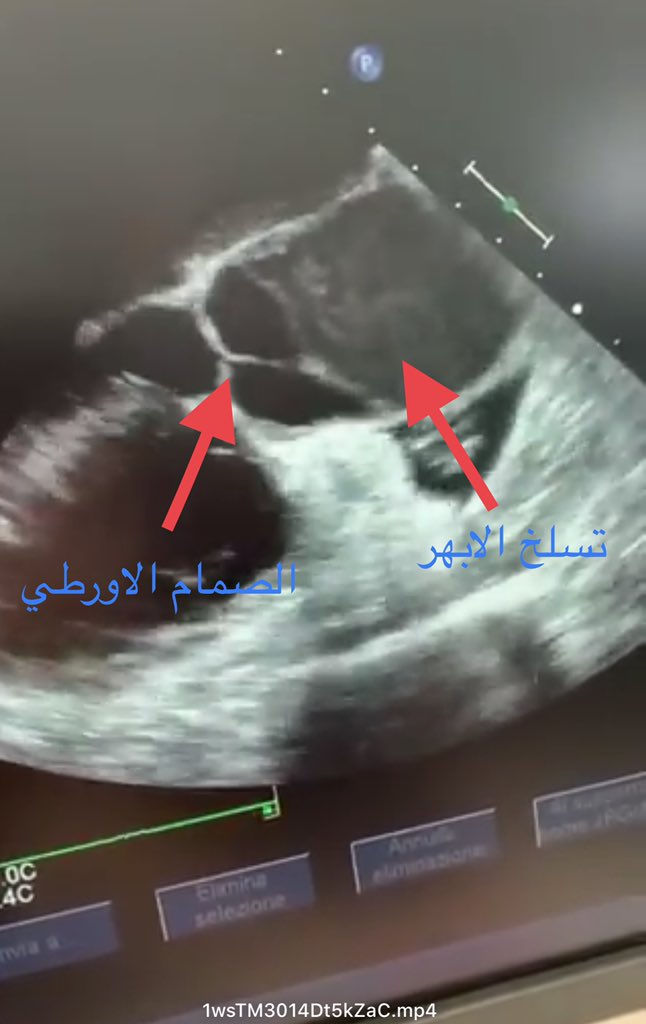

هده المقطع مأخوذ من الاشعة الصوتية للقلب "الايكو" والتي يتم عملها بالمنظار من داخل المريء.

يظهر في المقطع مايشبه الدخان smoke appearance والذي يدل على ركود الدم في القناة الغير حقيقة false lumen

حالة تسلخ للشريان الاورطي/ الابهري قبل وبعد التدخل الجراحي.

الصور من الزميل الفاضل د. حمد الحبيب @hamad_alhabib